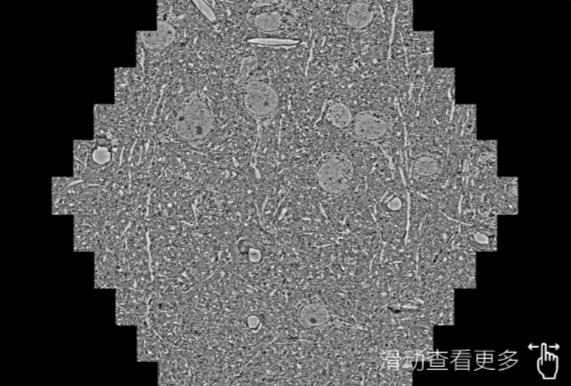

鼠脑切片。左图使用河南蔡司河南扫描电镜MultiSEM706对165μmx143pm面积区域成像,耗时仅需1.5秒。右图为鼠脑切片中30μm区域放大效果。样品由芝加哥大学B.Kasthuri提供。

使用蔡司高速河南扫描电镜MultiSEM对1mm²人脑皮层组织进行高分辨成像,并对其中的各种细胞结构进行三维重构分析。左图展示了2x3mm²组织平面中锥体神经元的三维重构效果。右图显示了局部体积神经元三维重构。图像由哈佛大学chtman实验室提供,渲染图由D. Berger 制作。